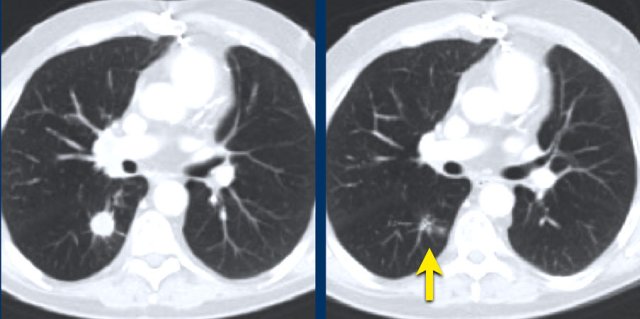

The images are of a patient with a primary lung tumour.

At baseline, the longest diameter is well above 10 mm, therefore this was assigned as a target lesion.

During follow-up the long-axis diameter dropped below 10 mm, which is the lower limit for considering a lesion as target lesion.

However, since this is a follow-up measurement, the target lesion still counts up to the sum of the diameters (SLD) and a default value of 5mm was assigned.